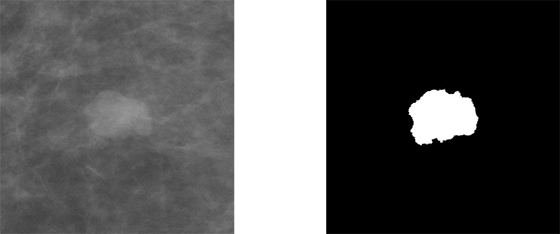

Pentru acest exemplu vom folosi setul de date (CBIS-DDSM, 2020) disponibil în Cancer Imaging Archive. Acesta conține mamografii și măști binare cu tumorile segmentate de radiologi. Luăm în considerare 1566 de pacienți, care pot avea una sau mai multe tumori. Acestea sunt de două tipuri: calcifieri (eng. calcification) și mase (eng. mass).

Figura 3 Exemplu de imagine și mască decupată